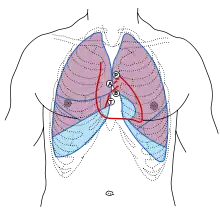

First heart sound: caused by atrioventricular valves - Bicuspid/Mitral (B) and Tricuspid (T).

Second heart sound caused by semilunar valves -- Aortic (A) and Pulmonary/Pulmonic (P).

Knowledge of the surface anatomy of the thorax (chest) is particularly important because it is one of the areas most frequently subjected to physical examination, like auscultation and percussion.[4] In cardiology, Erb's point refers to the third intercostal space on the left sternal border where S2 heart sound is best auscultated.[5][6] Some sources include the fourth left interspace.[7]